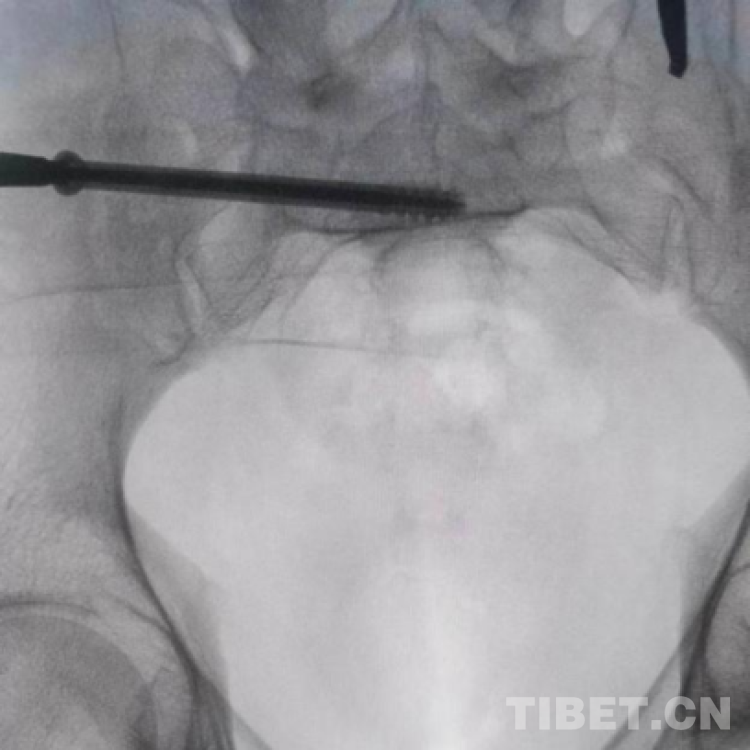

图为透视下见置入的骶髂螺钉,位置、长度精准,无丝毫偏差